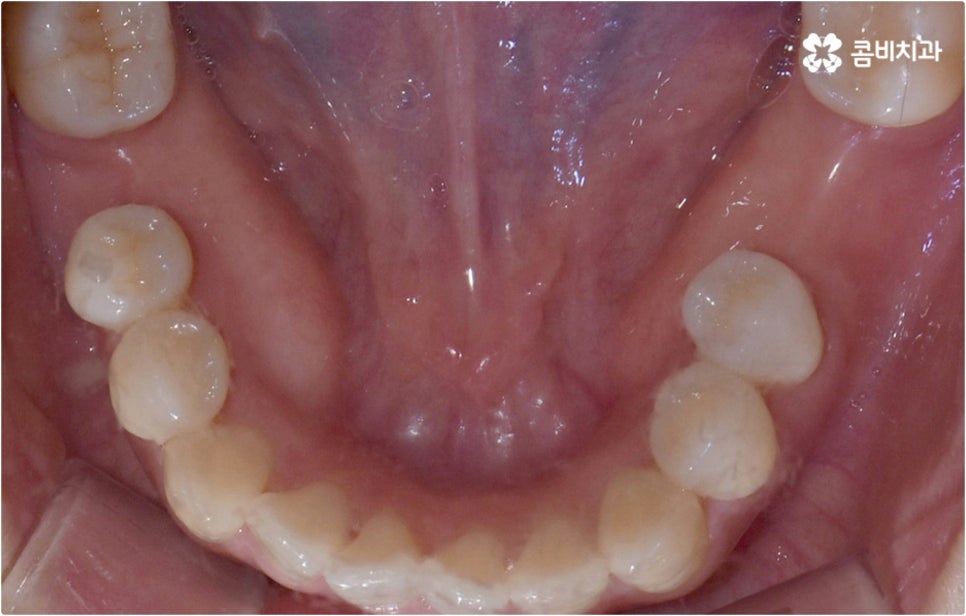

이런 때는 치아설측교정 대신 비교적 잘 보이는 윗니는 설측으로 진행하고, 입술에 가려 잘 보이지 않는 아랫니는 순측(입술쪽)으로 진행하는 콤비교정을 이용하면 발음, 이물감, 통증 문제를 해결할 수 있습니다. 콤비교정 시 치아 겉면에 부착하는 아랫니 브라켓의 경우 치아와 색상이 비슷한 세라믹 재질을 이용하기 때문에 심미성도 크게 떨어지지 않으며 치아설측교정 으로 전체를 진행하는 것 보다 비용적인 부담도 줄여주므로 설측 교정 치료를 생각하시는 분들이라면 콤비교정 역시 함께 알아보시길 권유드리고 있어요.

이와 같이 치아설측교정 과 콤비교정은 브라켓을 치아 안쪽으로 붙여서 치료하는 방식이기 때문에 굉장히 고난도의 복잡한 교정 치료라고 할 수 있습니다. 교정에 대한 높은 이해도와 해부학적으로 뛰어난 노하우, 풍부한 경험을 통해 축적한 세심한 기술력을 갖추고 있는 의료진에게 치료를 맡기는 것이 중요하며 정밀 디지털 검진 장비를 통한 정확한 검사 결과를 바탕으로 무리하지 않게 진행하실 필요가 있어요. 또한 양치질을 할 때 음식물 제거가 쉽지 않으므로 환자분들 본인이 평상시 신경써서 닦아주시는 것은 물론 꼼꼼한 케어시스템을 통해 주기적으로 관리해 주는 치과에서 교정 치료 및 사후 유지 관리까지 철저하게 받아보시길 권유드리고 있습니다.